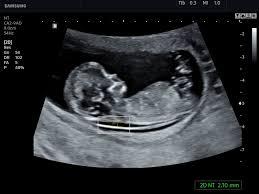

УЗИ во время беременности

УЗИ в 20 недель (во втором триместре/оценка анатомии плода): • Когда ожидаемая дата родов (менее достоверно, чем УЗИ на ранних сроках)? • Сколько там детей? • Развивается ли нормально ребенок ? • Существует ли подозрение на наличие каких-либо проблем у ребенка (оценка анатомии плода)? • Где находится плацента в матке? • Достаточно ли количество околоплодной жидкости?